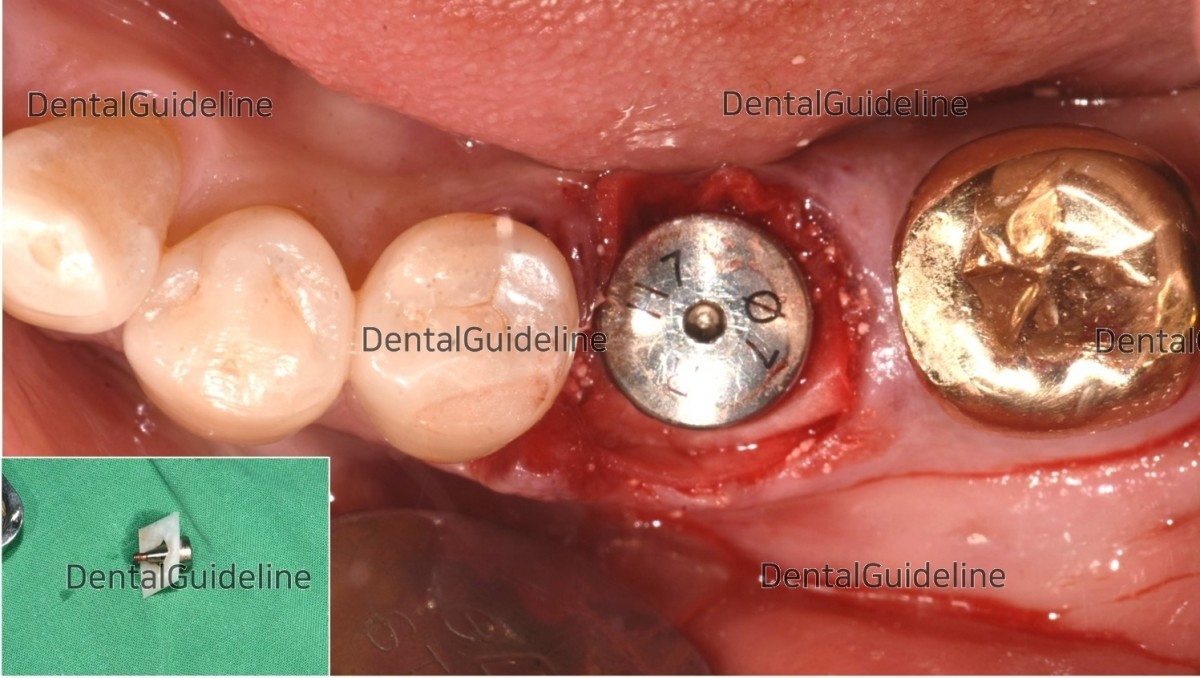

The collagen membrane-healing abutment assembly was connected to the fixture.

suture (blue nylon).